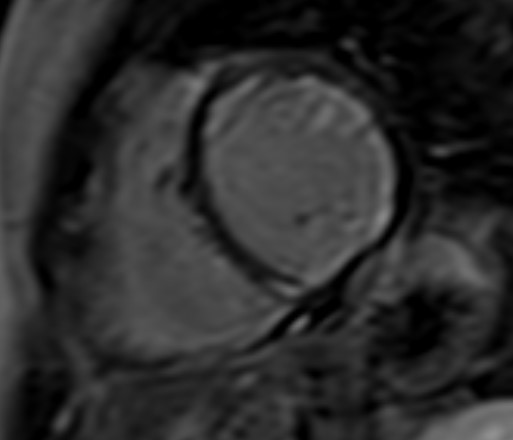

T1-weighted (T1-W) imaging is used for the anatomical assessment of the heart. Late gadolinium enhanced T1-W images (LGE), taken 8–15 min. After gadolinium-based contrast administration using inversion recovery pulse sequences, permit the detection and quantification of myocardial replacement fibrosis [11] (Fig. 5), if T2-W images in the same regions are negative.

Fig. 5.

Fig. 5.Replacement fibrosis evaluation using late gadolinium enhancement. Short axis with extensive late gadolinium enhancement (interventricular septum, anterior wall, inferior wall) in a patient with polymyositis and ventricular arrhythmias.